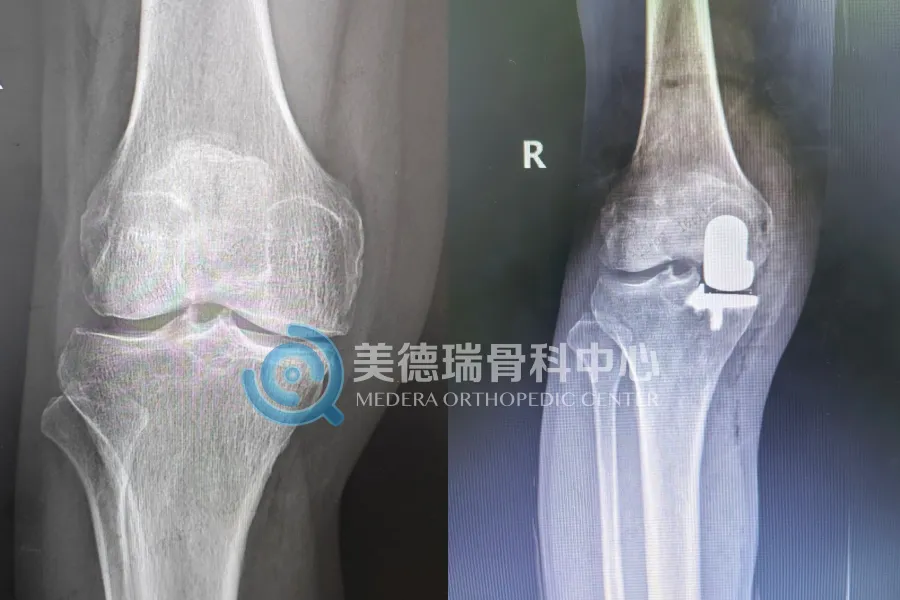

75岁的贾先生,膝关节退变局限于内侧间室,影像学显示其前交叉韧带功能完好,外侧及髌股关节软骨尚佳。对于这种“局限性”病变,团队并未采用传统的全膝关节置换,而是为他实施了单髁置换术(UKA)。这种术式只置换病损的内侧间室,保留了患者自身的韧带和正常的关节结构。